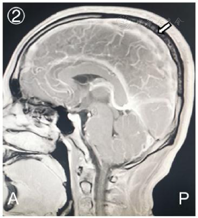

头颅CT:左侧额顶叶及右侧颞叶血肿,头颅MRV:颅内静脉窦血栓形成。

患者,男性,22岁,主因"头痛伴发作性抽搐、右侧麻木无力2 d"于2020年11月13日入院。入院6周前因工作原因进入高原地区(海拔5400m)执行任务,出现间断头部隐痛,考虑急性高原反应,给予常规对症处理后症状减轻。入院2 d前休息状态下出现头痛加剧伴右侧肢体麻木,否认意识障碍、恶心呕吐等症状,数小时后晕倒伴全身抽搐,发作数次,当地卫生院初诊为"癫痫",具体治疗不详,后转送至我院急救部。2020年11月13日头颅电子计算机断层扫描(Computed Tomography, CT)提示:左侧额顶叶及右侧颞叶血肿(图1);头颅核磁共振静脉成像(Magnetic Resonance Venography, MRV)提示:右侧颈静脉、乙状静脉窦、横窦及上矢状窦内信号不均(图2),考虑血栓形成。入院体检:体温36.9℃,脉搏84次/min,呼吸18次/min,血压136/75mmHg;意识嗜睡,反应迟钝,双侧瞳孔等大等圆、直径约2mm,反射灵敏,双侧额纹对称,右侧鼻唇沟变迁,伸舌偏右,颈阻阴性,右上肢肌力0级,右下肢肌力1级,左侧肢体肌力5级,四肢肌张力正常,生理反射正常,右侧巴氏征阳性。